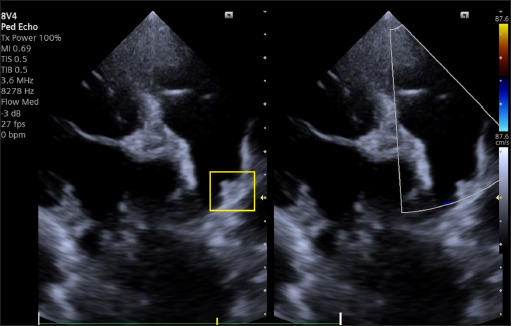

A transthoracic echocardiogram (TTE) (Siemens Acuson Juniper, Probe: 8V4, Siemens Healthcare, Erlangen, Germany) revealed mild left atrial and left ventricular dilation: Left atrium/aorta ratio: 1.8 ( reference value < 1.6), normalized to body weight), left ventricular internal diastolic diameter: 1.98 (reference value: ≤ 1.7), and left ventricle apical four-chamber view end-diastolic volume (Simpson biplane method): 23.6 mL (reference value < 20.1 mL), (Wess et al. 2021). It also revealed a small PDA, with approximate MDD and ampulla diameters of 1.2 mm and 3.7 × 7 mm, respectively, and a length of 7 mm (Fig. 2).

Fig. 2. Transthoracic echocardiography, cranial left lateral view, optimized for PDA visualization and its measurement (A) and and left-to-right flow on CFM Doppler (Dual-mode).